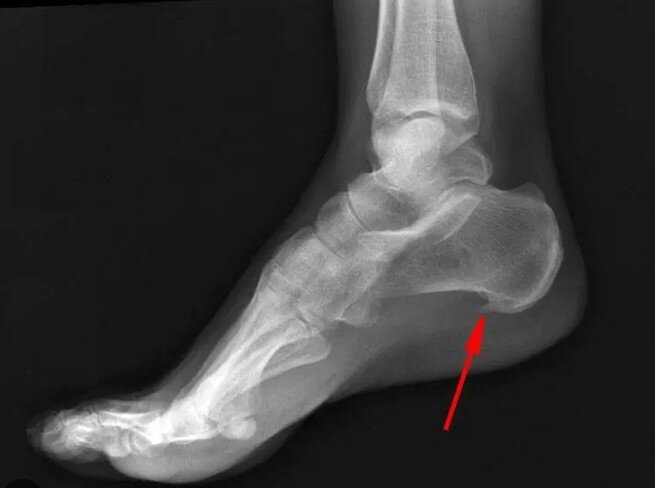

Снимок не мой, но наглядный